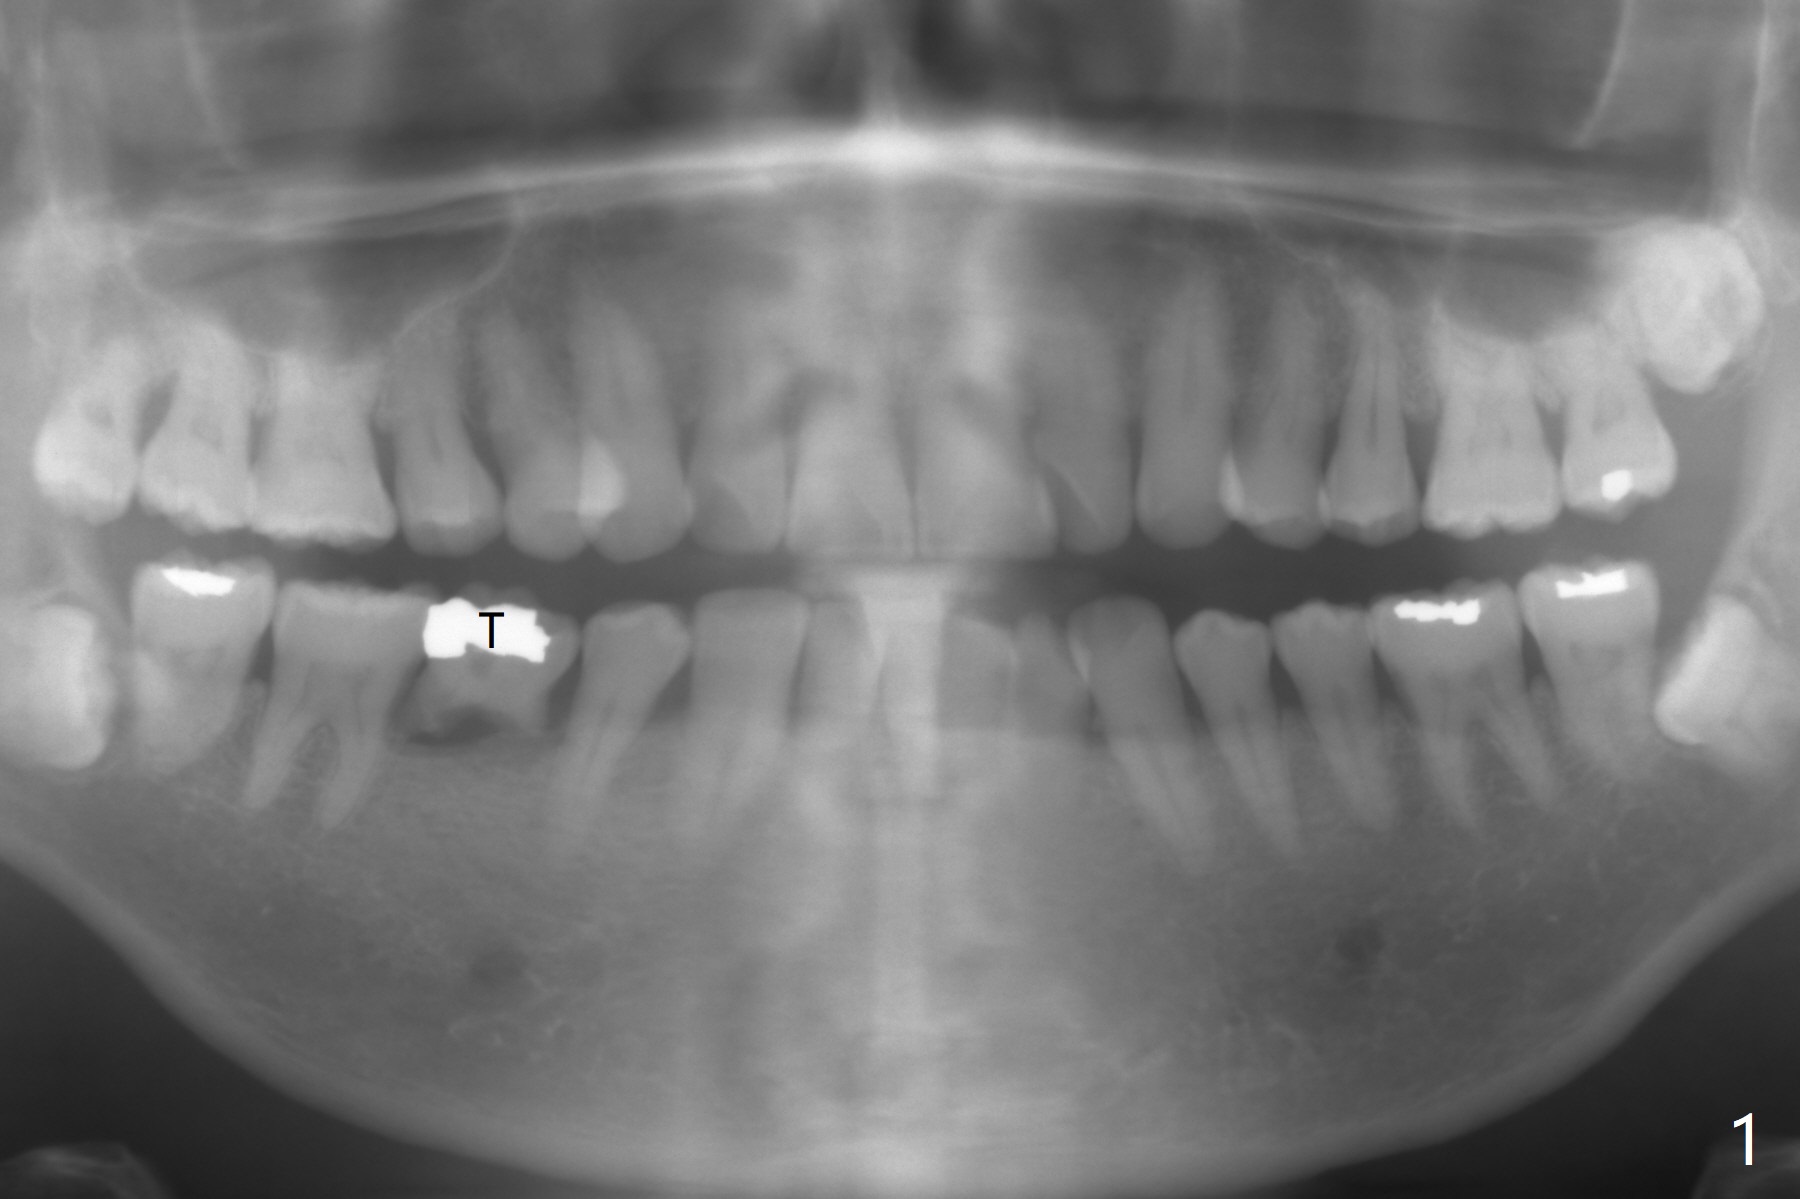

A 51-year-old man has a mobile 2nd primary molar (Fig.1 T).  The latter is much wider than the 2nd premolar.  Since there is crowding in the lower anterior region, it is the best to have limited orthodontic treatment to use the extra space at T to alleviate crowding anteriorly after implant osteointegration.  Although the patient has no intention for orthodontics, an implant will be placed distal (Fig.2 green).  To prevent periimplantitis, make sure that the implant is placed below bone.  Encourage the patient to brush normally over the provisional once there is no pain.  Use Rongeur to remove the septal bone before osteotomy.  Try IS implants if they arrive.